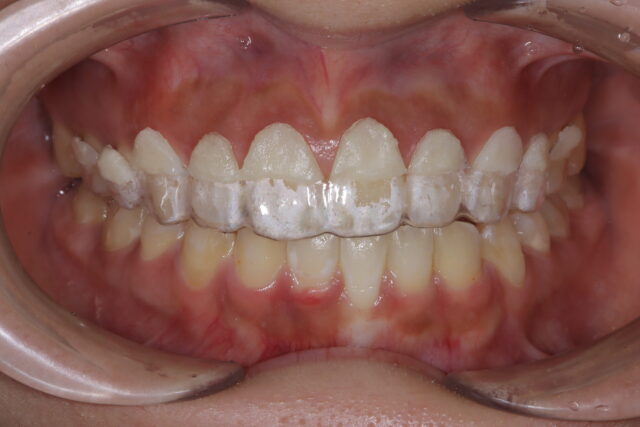

シミュレーション用マウスピース

術前にシュミレーションのマウスピースを装着し、患者様に術後の仕上がりシミュレーションを確認して頂いた後、オペに移ります。

精密なCTレントゲンより本当の歯の長さを計測し、それを元にシミュレーション用マウスピースを作製しました。

その結果、歯冠長延長術でガミースマイルが2.6mm改善することが分かりました。

治療後「歯が長くなると、変にならないのか?」そう思われる患者様が多いと思います。このシミュレーションマウスピースを見て頂くことで多くの患者様が安心して治療を受けて頂けます。

また0.1ミリ単位で作るシミュレーションマウスピースで過不足なく歯茎を切除することができます。